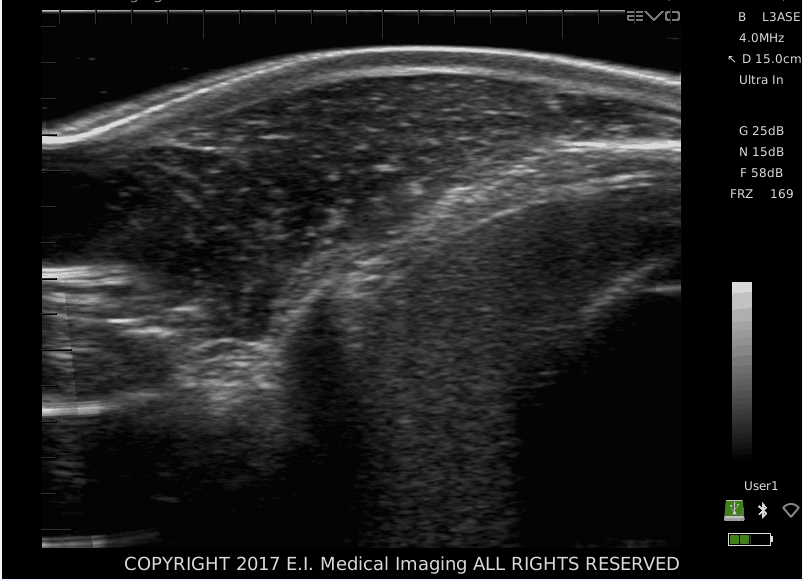

牛眼肌面积超声图像

通过观察直线阵列探头可以明显看出,对于腰眼肌肉区域的横截面扫描来说,某种类型的适应是必要的。因此,声学触点可作为每个单元的附件。 不同曲率的触点可用于牛肉或猪扫描。 触点很容易连接到探头上,并使用少量扫描凝胶来确保完整。扫描部位的触诊和声耦合剂(植物油)的应用。适用于维持扫描油的热电加热和冷却装置影响图像质量,尤其是在寒冷的气候下。当接触垫和声学凝胶也保持在油温附近时,可以获得***佳效果。每次使用后应使用温肥皂和水清洁垫,并将其存放在合适的容器中,以防止 柔性材料的损坏和干燥。如果按照建议保养和存放,垫子应该可以无限期地使用。